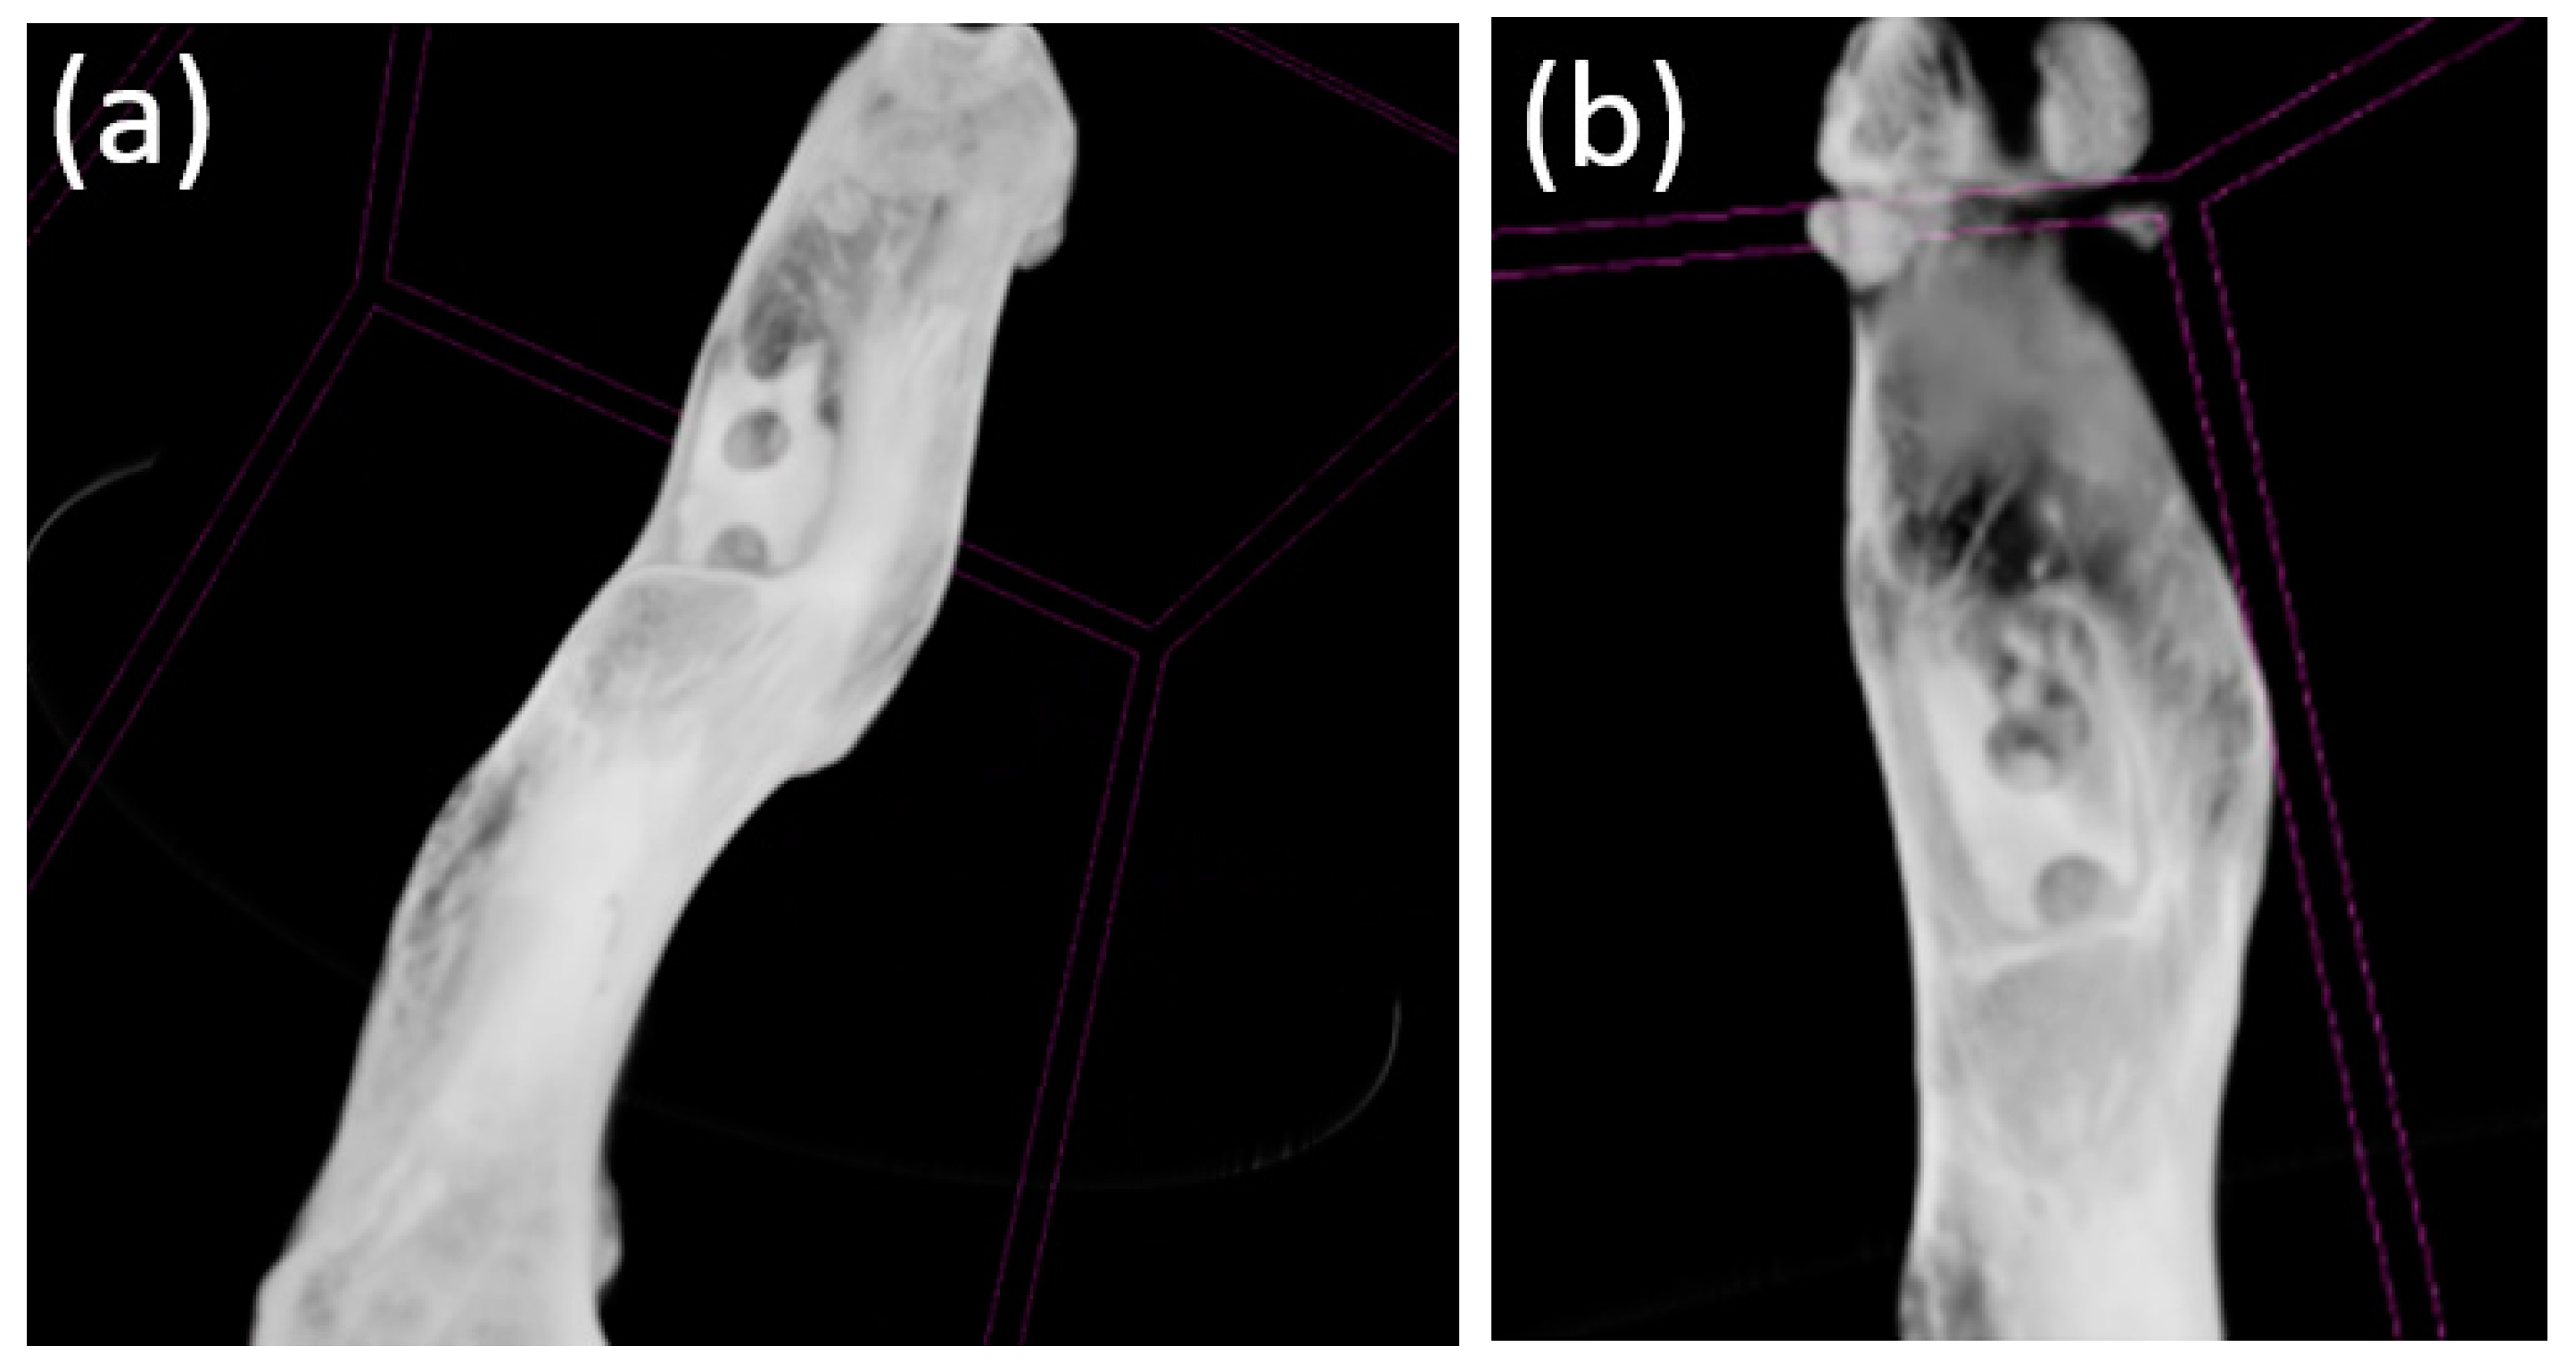

3.2. Ultrasound

3.3. X-ray Examination